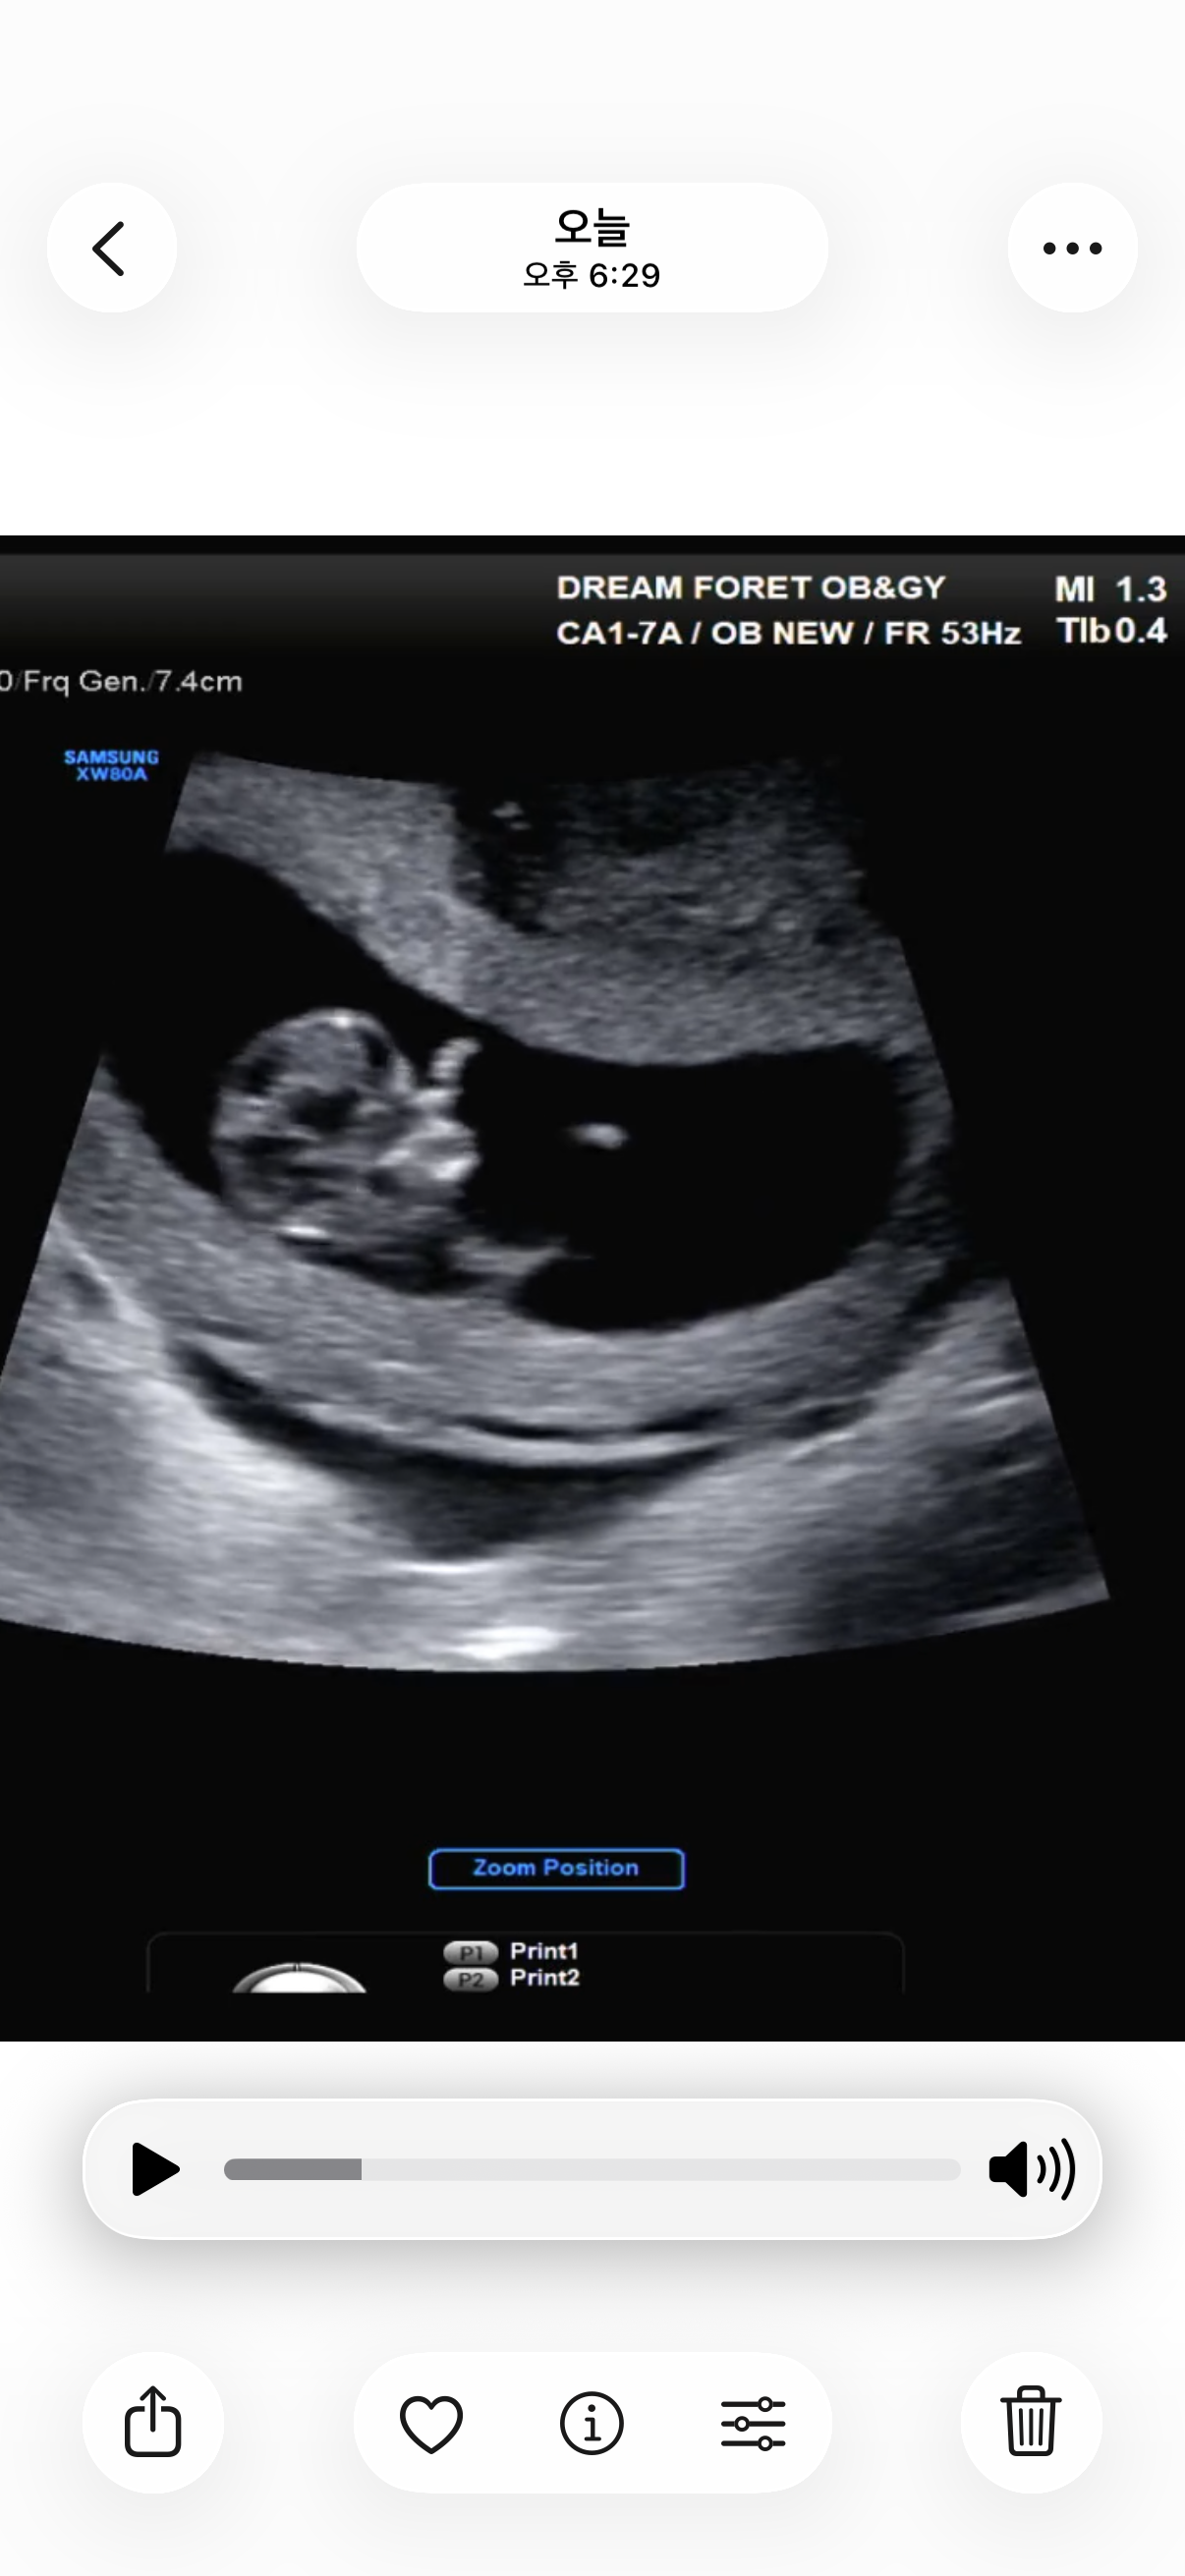

10주 아기 초음파

10주0일에 병원 가서 초음파 보고 왔어오 아기는 3.69cm 잘 크고 있다용~ 근데 이거 아기 얼굴 코 나온건가용?? 옆에 손으로 안녕 하는거 같아요 ㅋㅋㅋ 저만 그렇게 보이나욧.. 실제로 동영상으로도 만 움직이더라구영